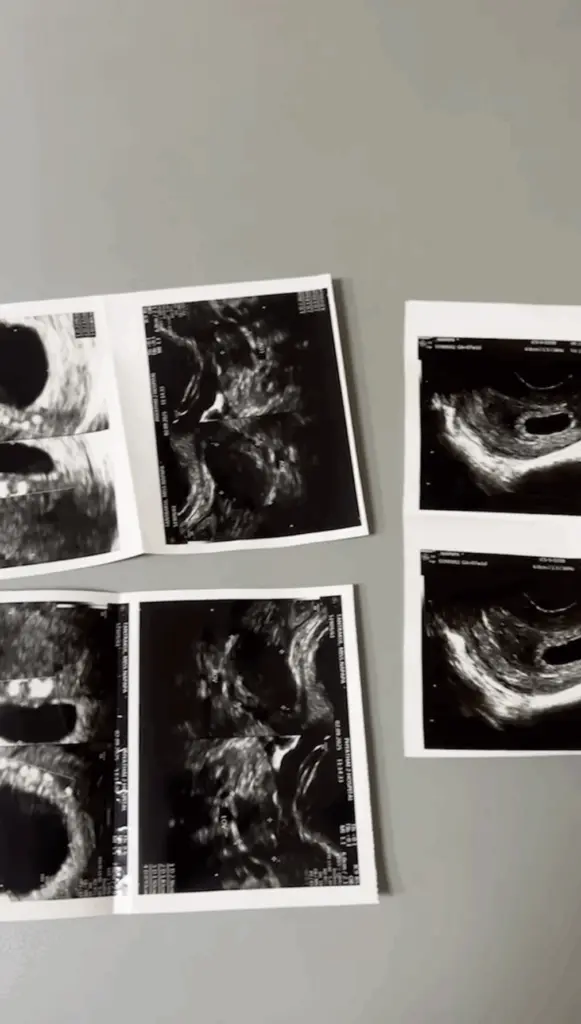

แต่แล้ว ความสุขก็กลายเป็นความเศร้า เมื่อเวลาผ่านไป แพทได้ไปอัลตราซาวด์เพื่อตรวจดูพัฒนาการของน้องในครรภ์ แต่ไม่พบตัวอ่อน ซึ่งคุณหมอบอกว่าอาจจะยังเล็ก หรือแอบอยู่ จึงให้รอดูอีกระยะ

จนกระทั่งเข้าช่วงเดือนที่ 3 แพทกลับไปตรวจกับคุณหม้าอีกครั้ง และได้รับคำยืนยันว่าเป็น “ท้องลม” ซึ่งคุณหมออธิบายว่าเกิดจากไข่ที่ไม่มีนิวเคลียส จึงไม่สามารถพัฒนาเป็นตัวอ่อนหรือเด็กได้